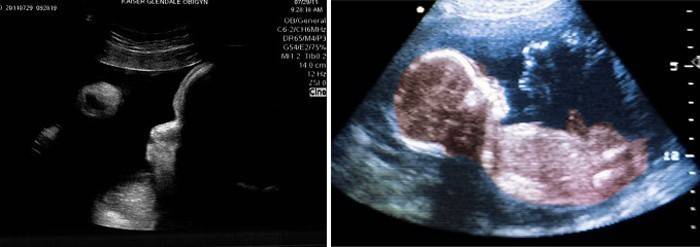

Ультразвукове дослідження (Узд)

На 39 тижні УЗД може знадобитися тільки для уточнення якихось нюансів і визначення тактики ведення пологів, його додатково призначає лікар. Лікар визначає термін вагітності на УЗД, можливий вага і ріст плода, всі його органи і тканини, ступінь зрілості і розвитку, а також дивись інші показники УЗД. Важливо оцінити стан матки та її розміри, зрілість шийки і її готовність, кількість навколоплідних вод і їх стан. Визначається ступінь зрілості плаценти – норма для цього терміну – третя ступінь зрілості, і чим вище ступінь, тим старіше плацента гірше її функції. Також важливо оцінити і знаходження і довжину пуповини – якщо вона розташована на шийці плоду, це потребує особливої уваги.

За даними УЗД і результатами обстеження вагітної можна виявити ознаки маловодия – воно для даного терміну буде фізіологічним, так як дає більш стабільне положення плода в матці, зменшує її розтягнення і запобігає випадання петель пуповини. При багатоводді матка може перерастягиваться, що призведе до слабкості родової діяльності і ускладнень. Точно встановити багатоводдя і маловоддя можна по УЗД, визначаючи кількість вод у мол.